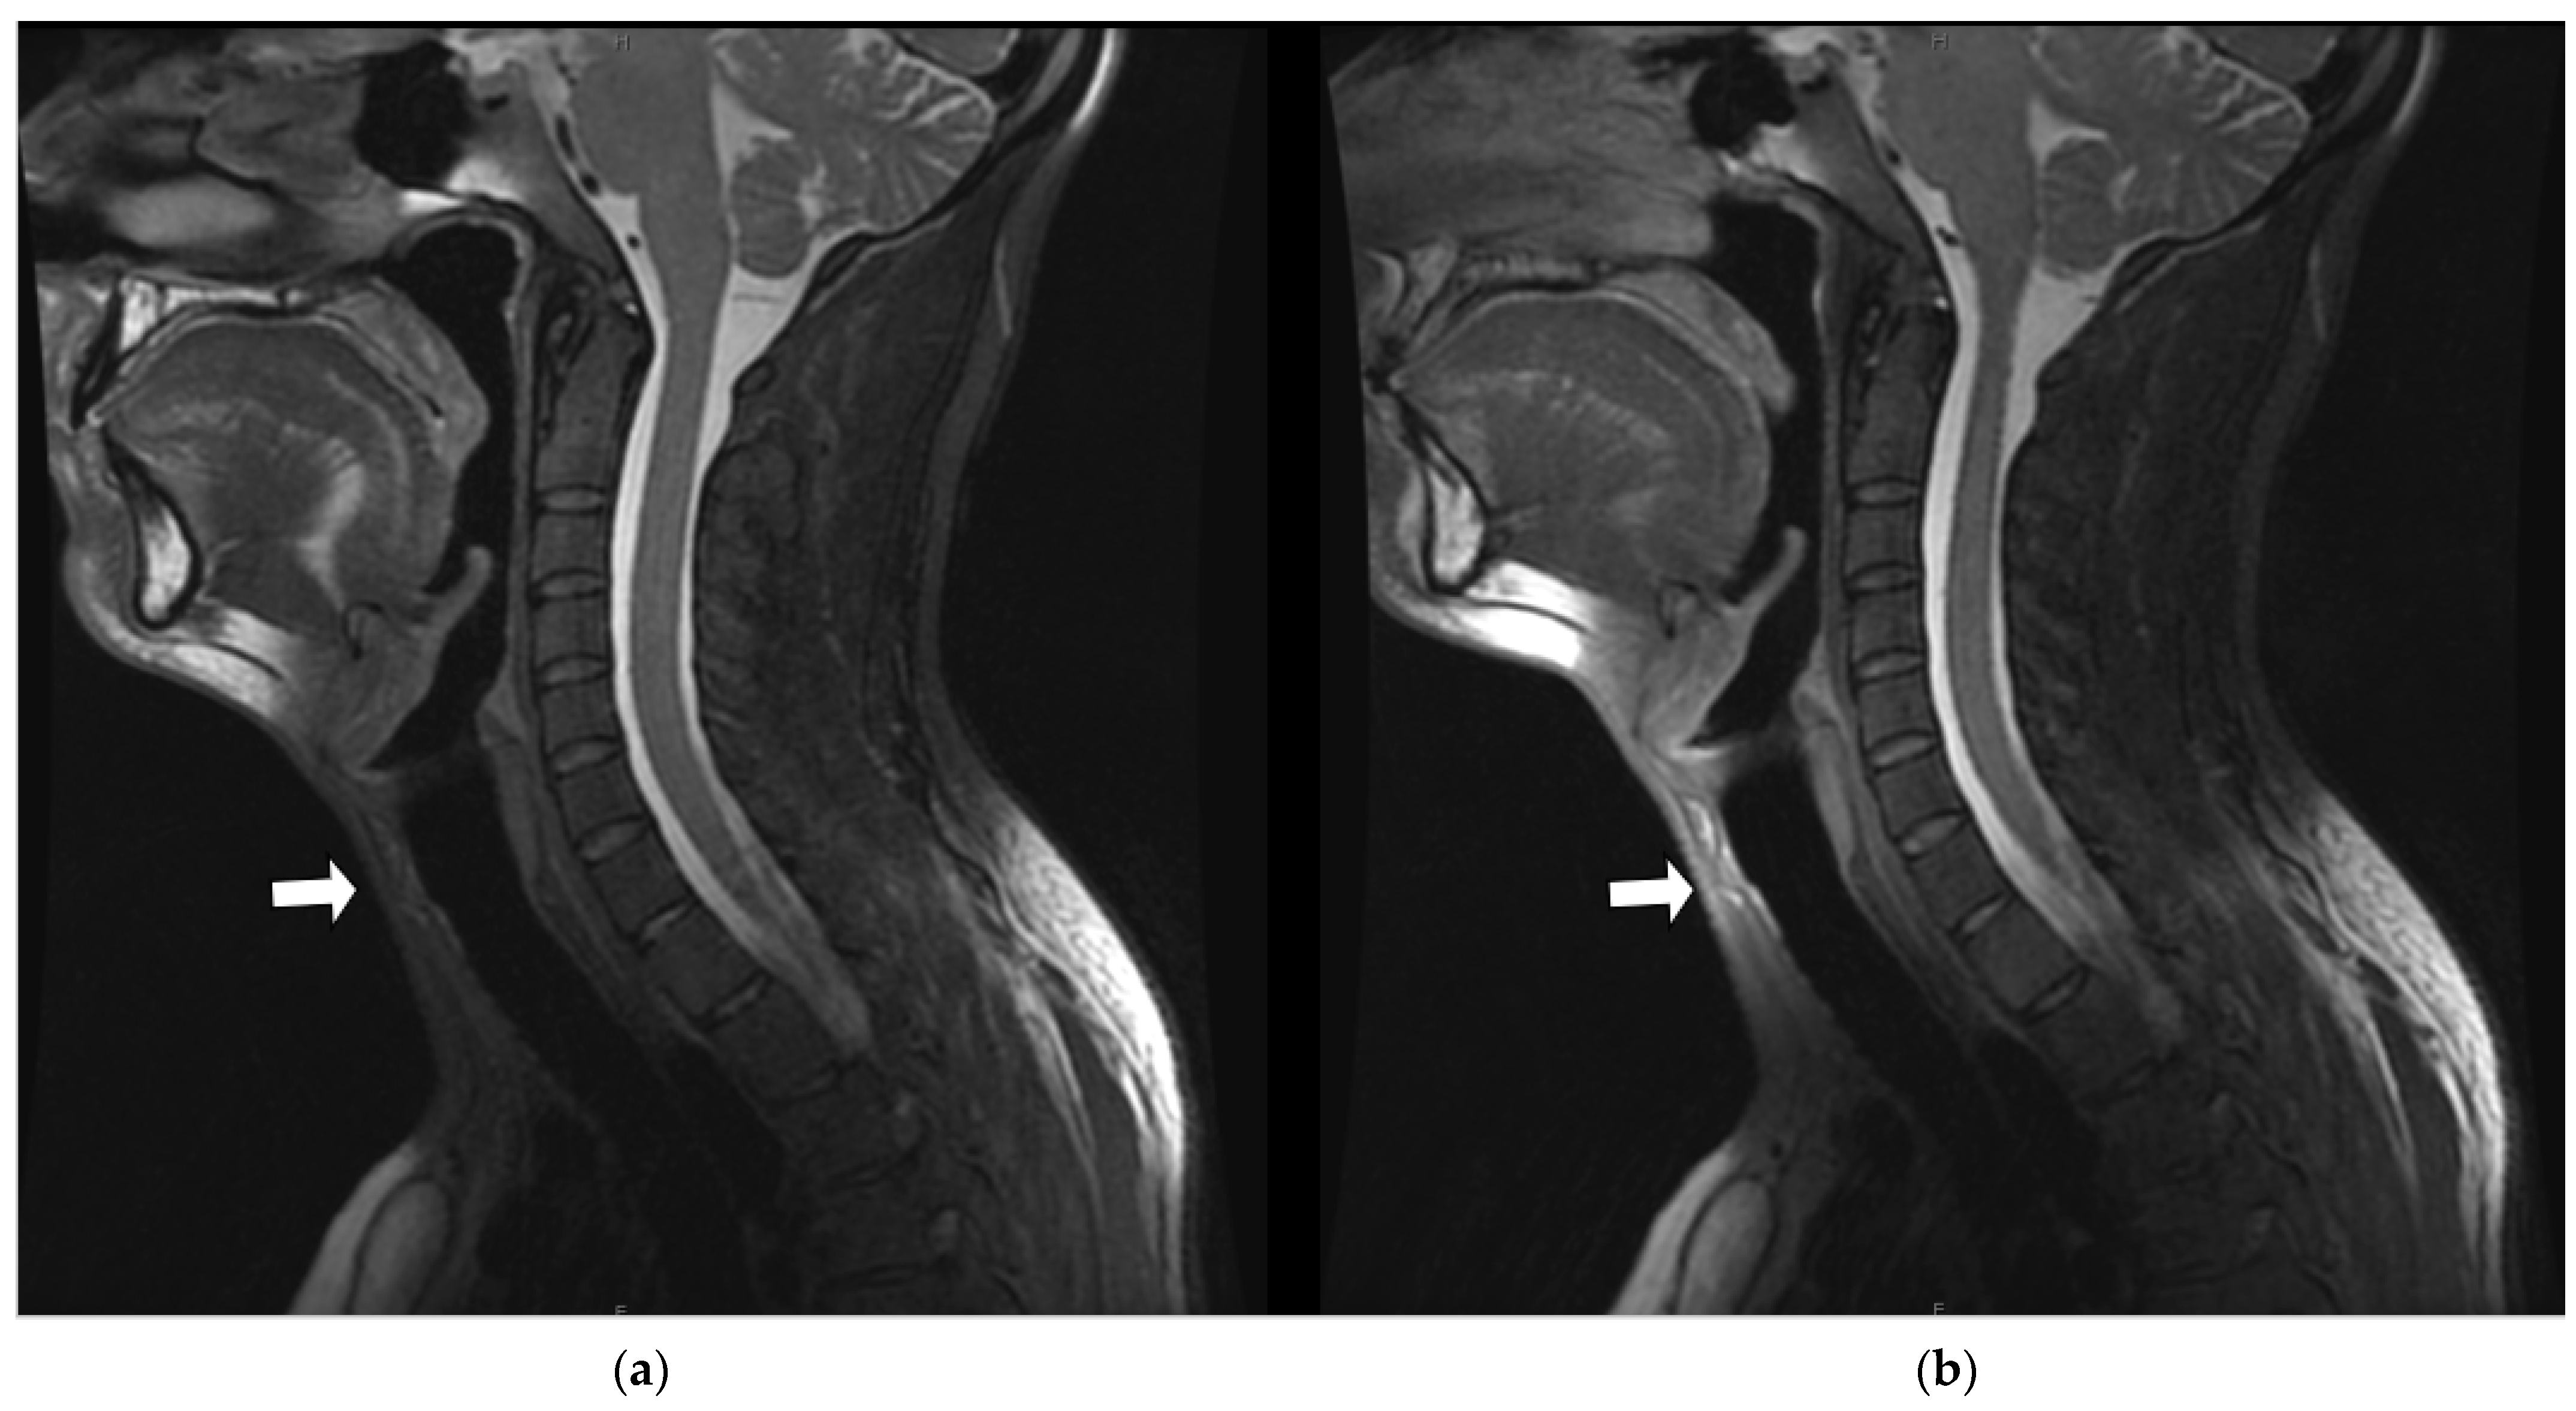

3.3.1. Margin Delineation